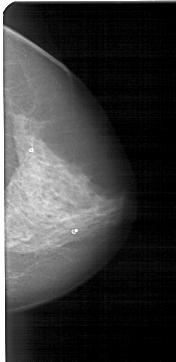

A_1316_1.RIGHT_MLO

RIGHT_CC LINES 4696 PIXELS_PER_LINE 2281 BITS_PER_PIXEL 12 RESOLUTION 43.5 NON_OVERLAY